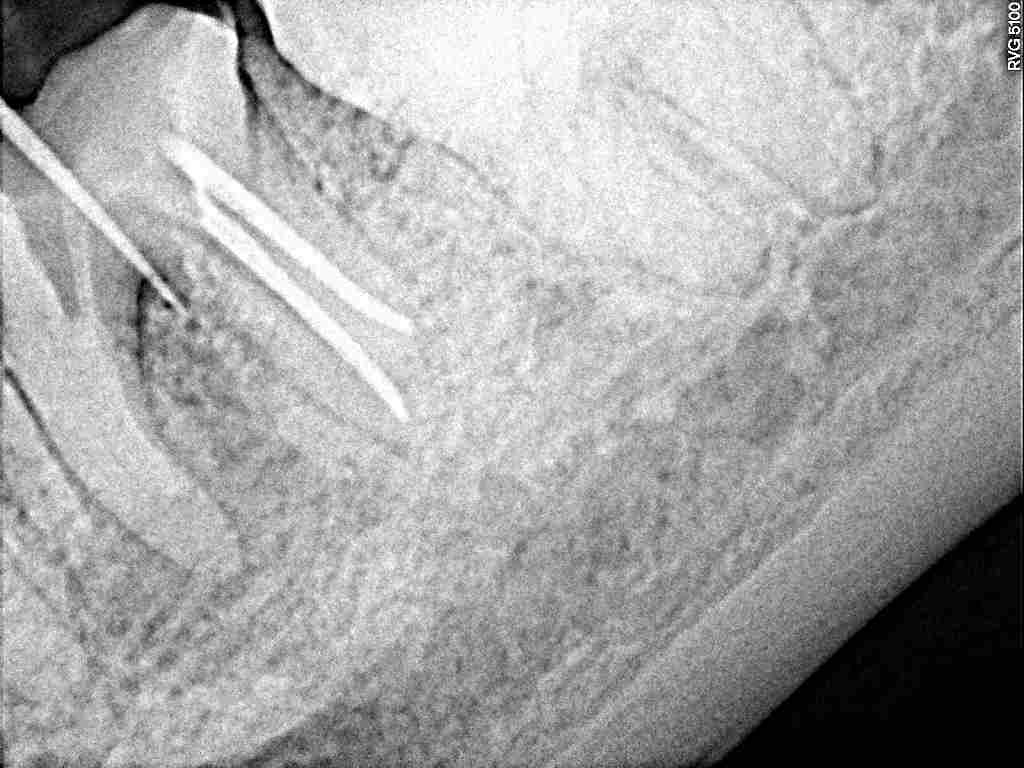

根の治療の難しさ 左下6番|お知らせ |広島市安佐南区の歯科医院 根の治療の難しさ 左下6番 トップ お知らせ・ブログ お知らせ 根の治療の難しさ 左下6番 根の治療の難しさ 左下6番 何年も前から腫れているのが気になって来院されました かなり上の方が腫れています 近心根が空きにくいようで分岐部まで黒い透過像となっています 近心根が明けれるかがカギとなります 髄床底にも交通するところが存在しました なので上の方が腫れてきます 根管を探していきました 根銃後になります 噛めるように修復して経過を見ていきます Web診療予約 初めての方へ 選ばれ続ける理由 院内設備について 歯が痛いしみる一般歯科 歯がぐらぐらする歯周病 健康な歯を保ちたい予防歯科 子供の虫歯予防をしたい小児歯科 銀歯をセラミックに審美歯科 白い歯を目指しませんか?ホワイトニング 矯正専門医がいるので安心矯正歯科 抜けた歯を補いたいインプラント・入れ歯 医院案内 スタッフ紹介 メリィハウス歯科クリニックオフィシャルホームページ ラベンダー歯科クリニックオフィシャルホームページ お知らせ・ブログ ホーム 診療科目 一般歯科 歯周病治療 予防治療 小児歯科 審美治療 ホワイトニング 矯正歯科 入れ歯・インプラント マウスピース矯正 初めての方へ 院長・スタッフ 設備紹介 医院案内・アクセス メニューを閉じる